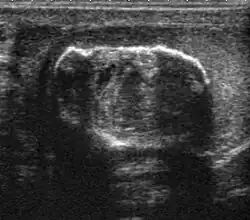

Undescended testis

Normally the testes begin its descent through the inguinal canal to the scrotum at 36 weeks’ of gestation and completed at birth. Failure in the course of testes descent will result in undescended testes (Cryptorchidism).

Undescended testis is found in 4% of full-term infants but only 0.8% of males at the age of 1 year have true cryptorchidism. Although an undescended testis can be found anywhere along the pathway of descent from the retroperitoneum to the scrotum, the inguinal canal is the most common site for an undescended testis. Deviation of testis from the normal pathway of descent will result in ectopic testis that is commonly seen in pubopenile, femoral triangle and perineal regions.

Besides infertility, undescended testes carry an increased risk of malignancy even for the normally located contralateral testis. The risk of malignancy is estimated to be as high as 10 times the normal individual with seminoma being the most common malignancy.

The incidence of infertility is decreased if surgical orchiopexy is carried out before the 1–3 years but the risk of malignancy does not change. Because of the superficial location of the inguinal canal in children, sonography of undescended testes should be performed with a high frequency transducer. At ultrasound, the undescended testis usually appears small, less echogenic than the contralateral normal testis and usually located in the inguinal region [Fig. 29]. With color Doppler, the vascularity of the undescended testis is poor.

-

Fig. 29. Undescended testis. (a) Normal testis in the scrotum. (b) Atrophic and decreased echogenicity of the contralateral testis of the same patient seen in the inguinal region.